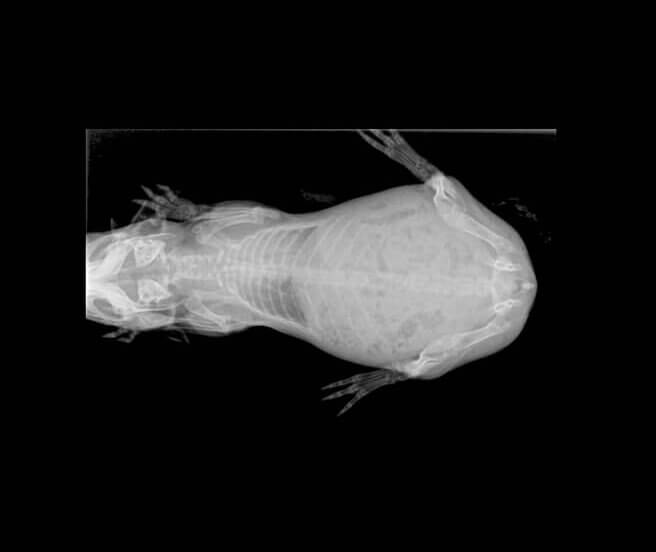

En el cas de l’Audrey, es va recomanar realitzar un cultiu fúngic i una radiografia, ja que les nostres sospites principals eren que patia algun procés respiratori i una infecció de la pell causada per fongs (dermatofitosi).

Una vegada realitzades les proves, es varen confirmar les nostres sospites. Audrey patia una dermatofitosi juntament amb una pneumònia localizada al pulmó dret.